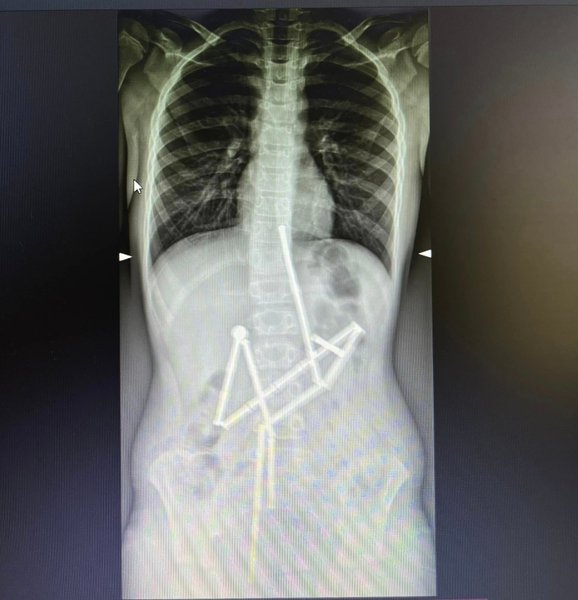

Як розповідається у релізі медиків, до "Охматдиту" звернулися батьки дитини, котра скаржилася на біль у животі. Після збору анамнезу та огляду фахівці відділення екстреної медичної допомоги направили хлопчика на інструментальне обстеження. Вже на першому рентген-знімку фахівці побачили у травному каналі цілу групу сторонніх тіл, в яких вдалось впізнати магнітний конструктор.

"20 магнітів були розташовані в різних частинах шлунково-кишкового тракту, проте зʼєднані між собою", — повідомили в лікарні.

Тож лікарям вдалося захопити перший магніт і витягти його разом із ланцюжком з 18 елементів конструктора. Проте один магніт залишився і фахівці не мали змоги видалити його ендоскопічно. Надалі за операційним столом почали працювати хірурги.

"Була виконана лапаротомія та ретельна ревізія органів черевної порожнини. Під час цього в дитини було виявлено п’ять перфоративних отворів та останній елемент конструктора. Всі отвори були закрито, а магніт видалено", — йдеться далі в повідомленні.